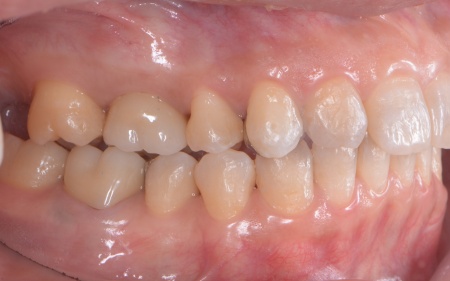

50代女性 インプラント・矯正・被せ物治療で見た目と噛み合わせを改善した症例

「以前治療した左下奥歯が思うように噛めない。また、矯正治療を受けた前歯でうまく噛めない」とご相談いただきました。

拝見したところ、左下奥歯(第1大臼歯)は以前、歯根分割処置が行われていました。

さらに患者様は全体的に歯並びや噛み合わせに問題があり、特に上下の前歯は噛んだ際に隙間ができ食べ物を噛み切りにくい状態です。

過去に矯正治療を受けていても、治療が不十分であったり治療後に歯並びが後戻りしたりすることで歯並びが乱れる場合があります。